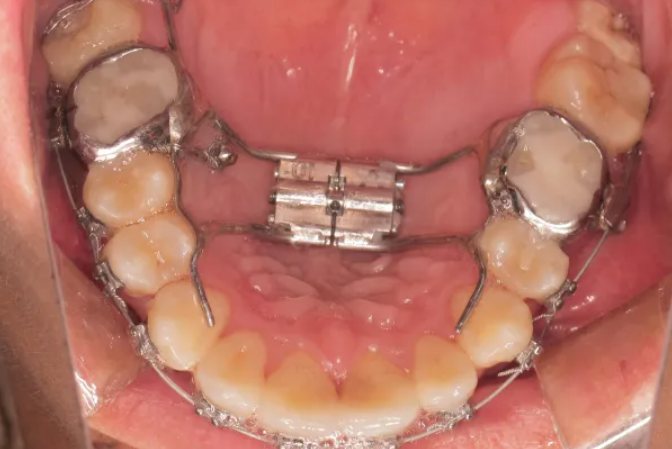

1、螺旋扩弓器

螺旋扩弓器有良好的固定装置,常选用带环或整个上颌后牙平面式颌垫夹板,并采用粘接方法,将矫治器固定于上牙弓上。